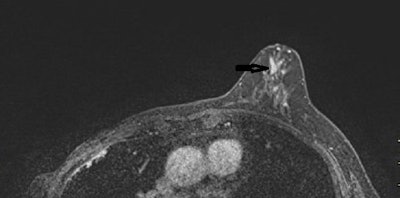

MRI demonstrates superb performance in identifying breast lesions where surgical removal is required for women with suspicious nipple discharge, according to new research published April 13 in European Radiology.

The study authors, led by Dr. Martine Boisserie-Lacroix from Institute Bergonié in France, found that MRI has "excellent" sensitivity and negative predictive value for detecting a lesion requiring excision in patients who had otherwise normal mammograms and ultrasounds.

The current study covered 102 patients in a multicenter trial that took place between 2013 and 2019. In all, 48 patients had lesions requiring excision. By using MRI, the research team identified 46 of these.

Performance of MRI for detecting cases of nipple discharge requiring excision | |

Sensitivity | 96% |

Specificity | 85% |

Positive predictive value | 85% |

Negative predictive value | 96% |

Focusing on malignancy, MRI's negative predictive value and sensitivity were 100%.